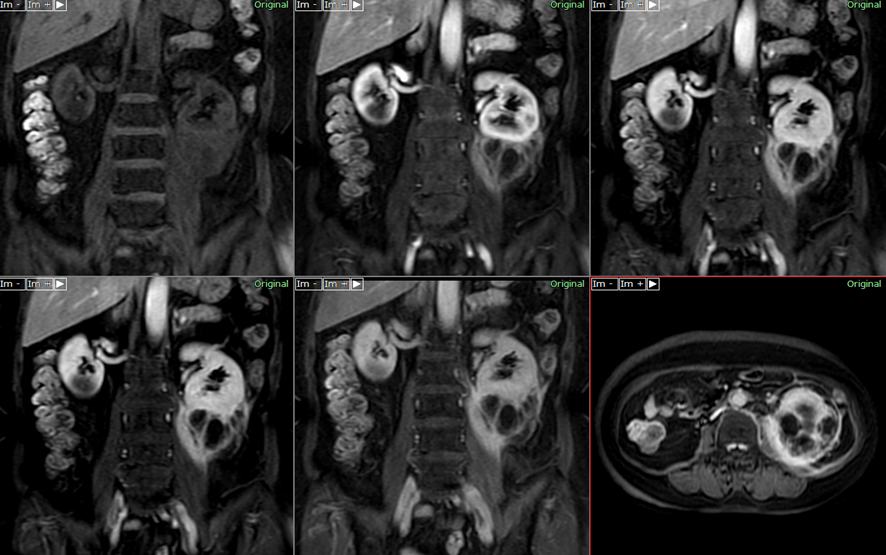

他のタイプのRCCと同様に、CCPRCTの診断には通常、一連の検査と手順が含まれます。通常、これには身体検査、臨床検査、および画像検査が含まれます。画像検査の例には、 CT 、 MRI 、超音波スキャンなどがあります。